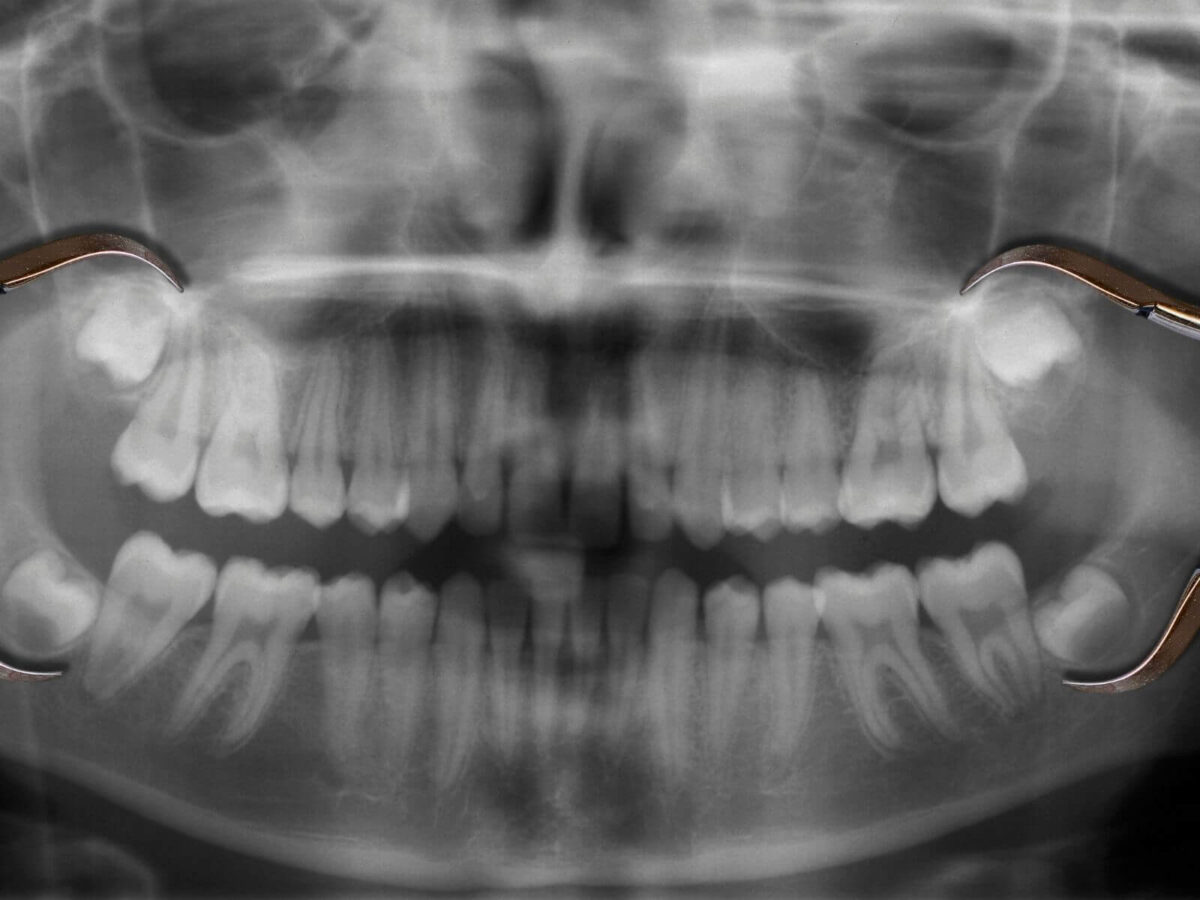

Your dentist can see quite a bit during a visual exam. But what they can’t see is what’s going on inside your teeth or under your gums. That’s where X-rays do all the heavy lifting. They help find small cavities tucked between your teeth. They show infections at the root or bone loss long before you feel a single thing. You might feel fine, but that doesn’t always mean everything is okay.

At Mathis Dental Office TX, these quick scans have helped us catch issues early. Without them, those same issues could’ve turned into root canals, extractions, or worse.